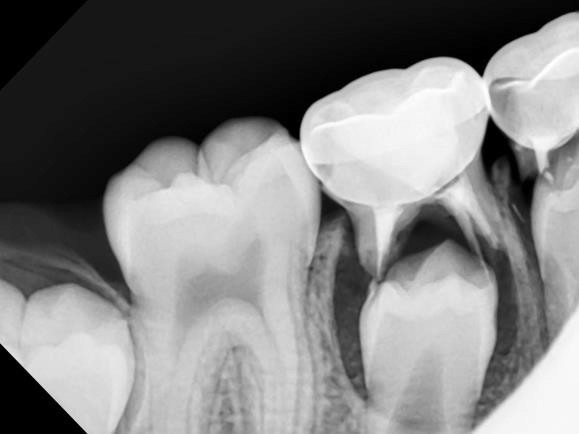

Dark Gum Spots & Teething

Occasionally, a swollen spot known as an eruption hematoma can form over a child’s erupting tooth. When this small, fluid-filled cyst contains blood it appears dark blue or purple. The word “hematoma” refers to an area filled with blood, just like any bruise you might get from bumping your knee or elbow. This is a harmless lesion that requires no treatment and will disappear as the tooth grows into the mouth.